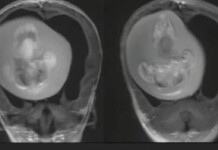

Menina passa por cirurgia para retirar feto de irmão gêmeo do crânio

Uma menina chinesa de 1 ano passou por uma cirurgia delicada para retirar o feto de seu irmão gêmeo do cérebro. O embrião ficou...